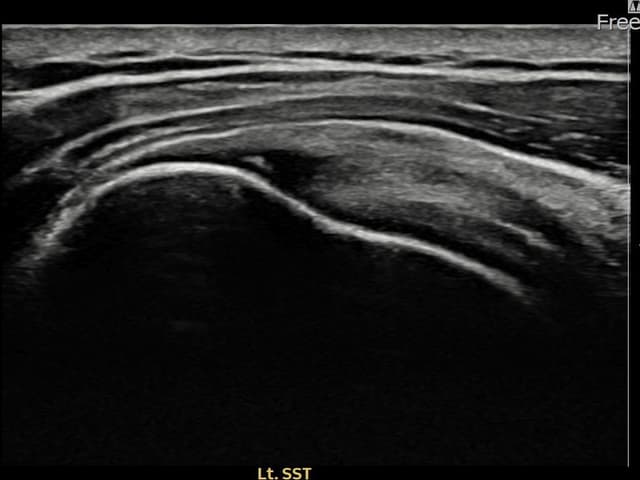

[経過期間: 23.07.18~23.09.14]

[縫縮術] 超音波検査にて左 棘上筋腱 광범위 部分断裂(15mm × 6mm (腱厚の約70%欠損))を確認。縫縮術施行後、腱の連続性が回復し、日常生活に復帰されました。